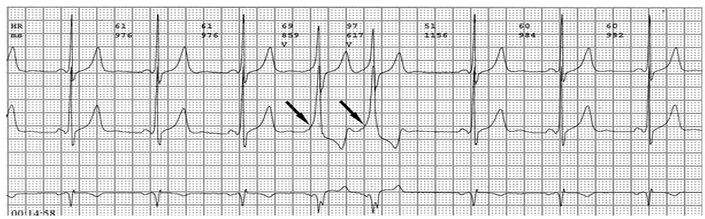

各旁路引起预激的心电图特征如下:

1、房室旁道

(1)PR间期(实质上是P-δ间期)缩短至0.12秒以下,大多为0.10秒;

(2)QRS时限延长达0.11秒以上;

(3)QRS波群起始部粗钝,与其余部分形成顿挫,即所谓预激;

(4)继发性ST-T波改变。

上述心电图改变尚有分为A、B两型的。A型的预激波和QRS波群在V1导联均向上,而B型V1导联的预激波和QRS波群的主波则均向下;前者提示左室或右室后底部心肌预激,而后者提示右室前侧壁心肌预肌。这种分类方法虽然受到预激是不同部位旁路所致的多变QRS波群的限制,但有助于区别旁路的心室端在左或右、前或后,因而沿用至今。

1、典型预激综合征

(1)P-R间期<0.12秒,P波正常;

(2)QRS时间>0.11秒;

(3)QRS波群起始部分变粗钝,称为预激波δ波

(4)继发性ST-TT改变。临床上又分为两型:A型预激:预激波和QRS波群在V1导联向上,其旁道位于左侧房室瓣环周围。B型预激:预激波和QRS波群的主波V1导联向下,在左胸导联V5向上,其旁道位于右侧房室瓣环的周围。